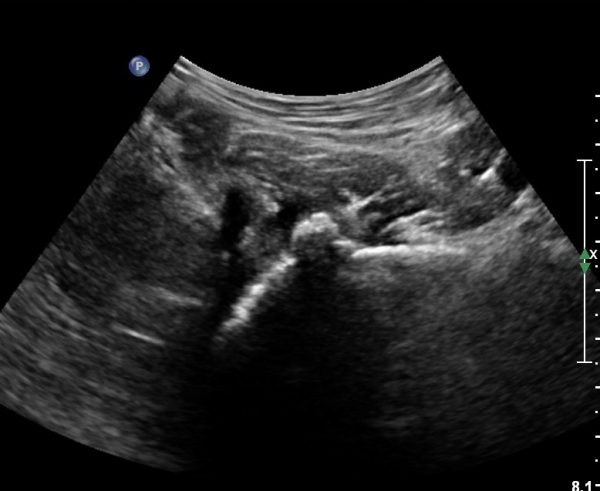

[¾ûµ¢ÀÌ] ¾ûµ¢ÀÌ °üÀý¼ø ÆÄ¿­ÀÇ ÃÊÀ½ÆÄ°Ë»ç(ultrasonography of labrum tear of hip joint)

Sonography of the Acetabular Labrum Visualization of Labral Injuries During Intra-Articular Injections

Sonographic evaluation of anterosuperior hip labral tears with magnetic resonance arthrographic and surgical correlation.